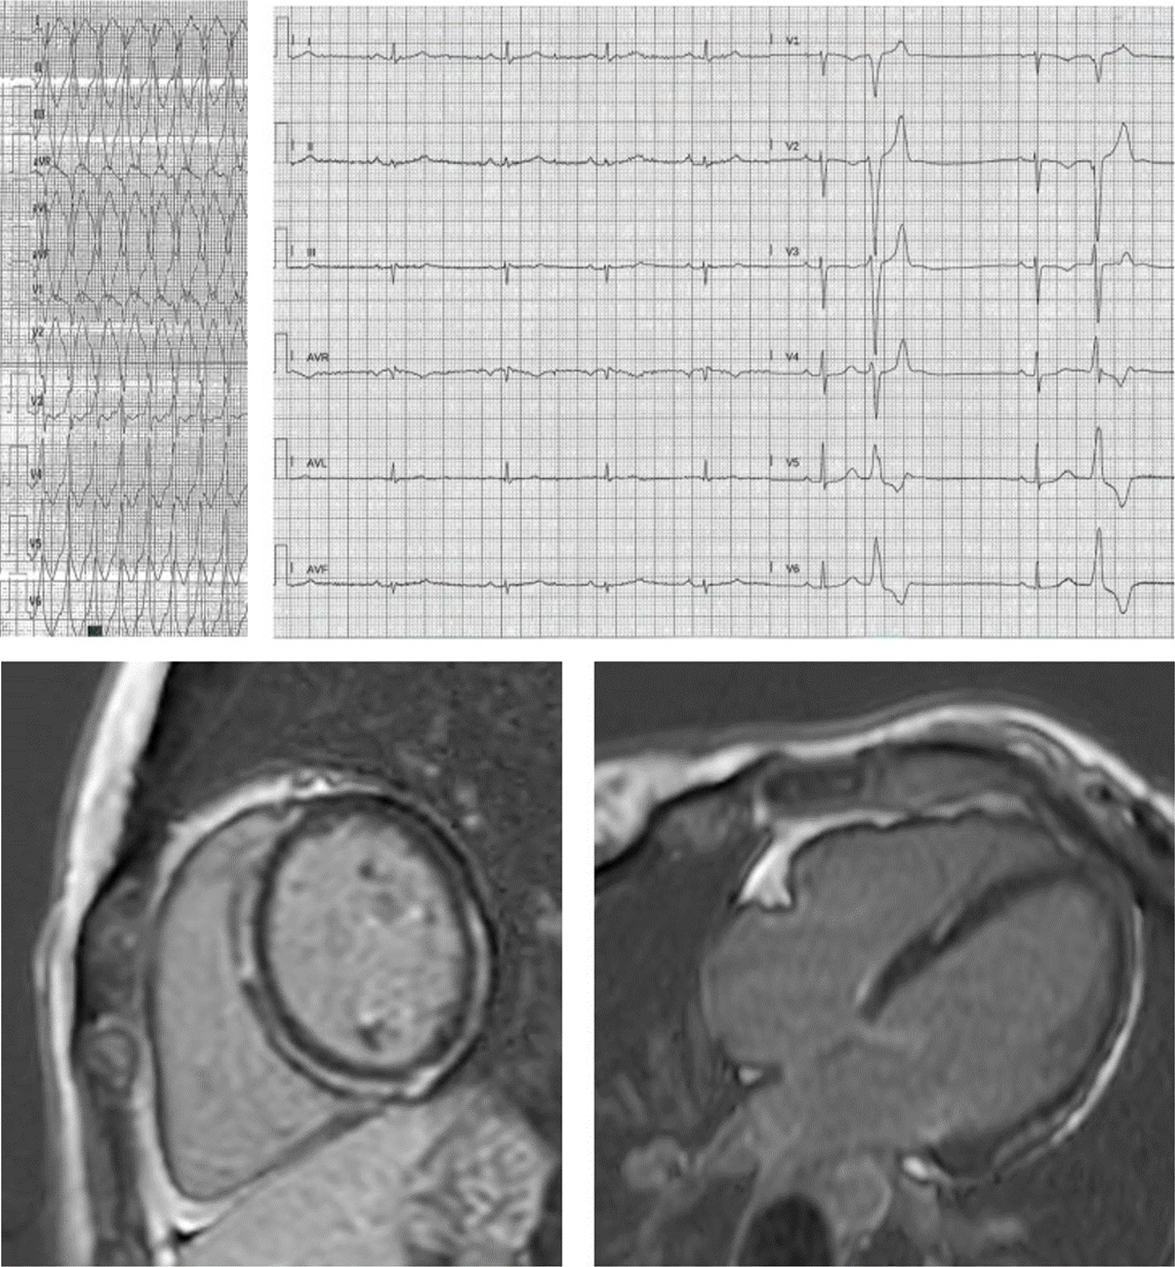

Fig. 1.Late-onset biventricular ACM in a 54-years old lady with self-terminating syncopal ventricular tachycardia, screened at 44 as mother of an ALVC proband, both with desmoplakin mutation. While ECHO and ECG were normal at 44, CMR at 54 shows: (A) fibrofatty infiltration located in subepicardic lateral wall of the LV. (B,C) Ring-like LGE located in the inferior wall and in the inferior interventricular septum. (D) Lateral wall focal areas of LGE and mild RV enlargement with anterior hypokinesia. (E) Inferior wall LGE. (F) RVOT bulging. See fragmented QRS mimicking a pseudo-epsilon wave in inferior limbs (negative in aVL) at ECG.

Fig. 2.Proband, aged 27 years, desmoplakin mutation: poorly tolerated monomorphic VT during training. See a midlayer ring-like fibrotic tissue involvement of the LV, without RV involvement. ECG shows low-amplitude limb leads with multifocal ventricular beats stemming from the anterior LV wall.